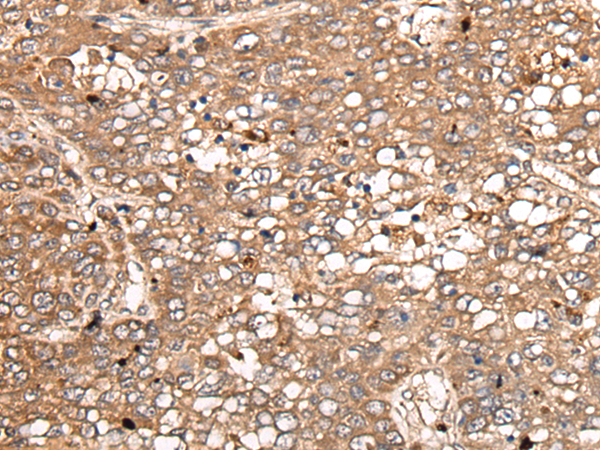

分类: 科研抗体货号: P05820别名:应用: WB,IHC反应种属: Human, Mouse, Rat